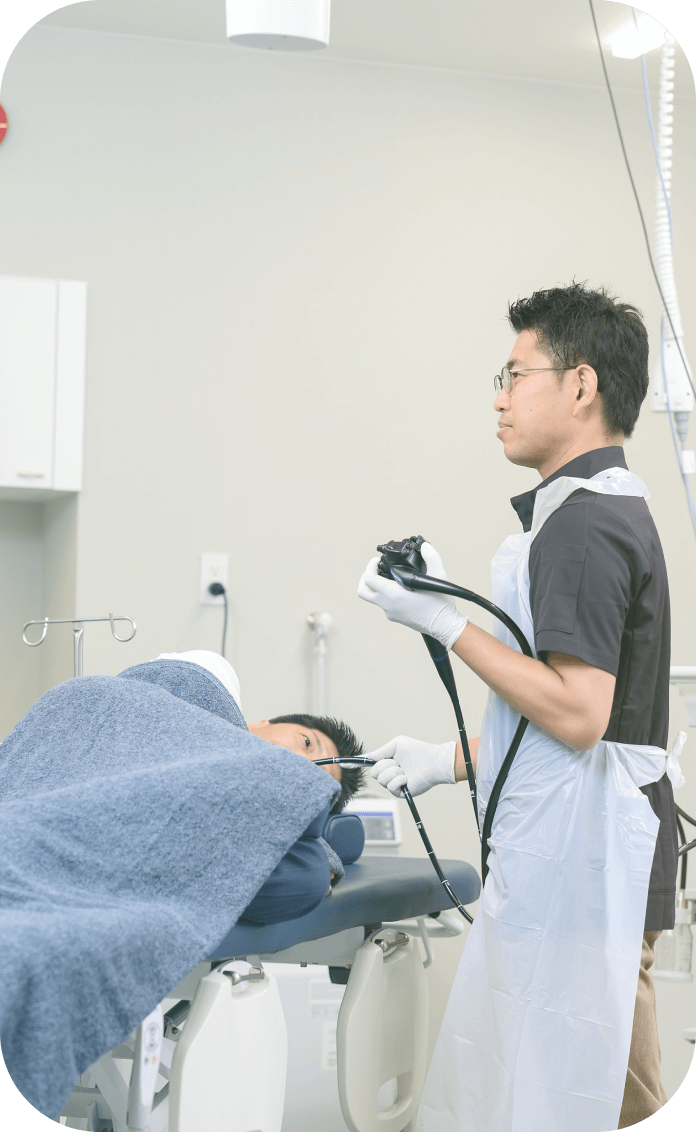

内視鏡のご案内

当院では、豊富な経験を持つ医師が高精度の胃カメラ検査および大腸カメラ検査を実施しております。鎮静剤の使用など、患者様の内視鏡検査による苦痛を最小限に抑える工夫をしておりますので、どうぞお気軽にご相談ください。